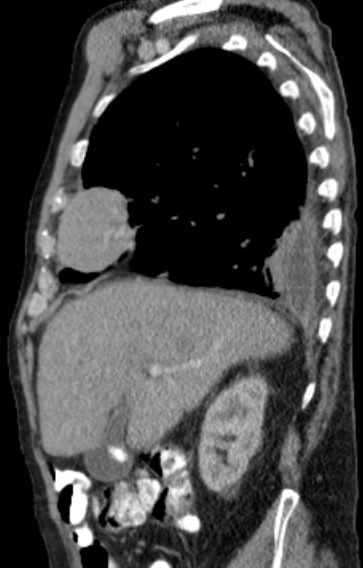

| Thorax | 76-jähriger Mann mit Herzinsuffizienz, Niereninsuffizienz und Pleuraerguss beiderseits.

Das CT zeigt eine intrathorakale Raumforderung rechts ventrolateral.![]() |

| Metastasierung | Lungenmetastasen und Lokalrezidiv 1 Jahr nach Leiomyosarkom der rechten Beckenwand.

![]() | ||